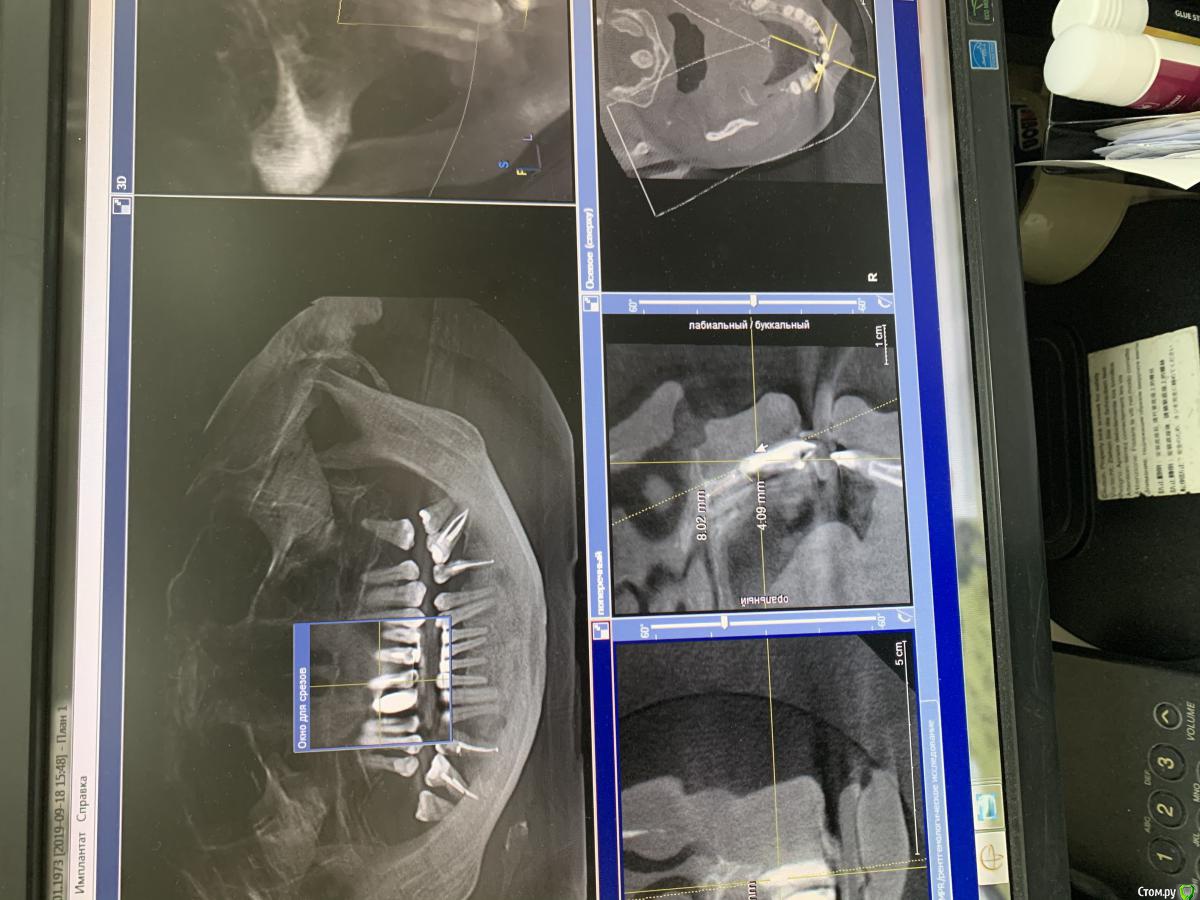

pavlin Опубликовано 12 ноября, 2019 Поделиться Опубликовано 12 ноября, 2019 (изменено) Планируется удаление 11 21 22 и имплантация в этой обл . Импланта в обл 12 ставили в др клинике несколько лет назад . Вопрос - тк кость в обл зубов ушла практически полностью , ставить Имплант как вОбл 12 (до носовой пазухи 8 мм ) тогда колонковая часть получается огромной ? Изменено 12 ноября, 2019 пользователем pavlin Ссылка на комментарий

pavlin Опубликовано 13 ноября, 2019 Автор Поделиться Опубликовано 13 ноября, 2019 ИМХО тут в руки щипцы и планировать с ортопедом высоту гребняА нормально будет , что Импланта высота 7-8 мм , а коронковая часть более 20 мм? Не вывернет ли имплант? Плюс по диаметру проходит только слим . Получается тонкий короткий Имплант и огромный рычаг в виде коронки Ссылка на комментарий

Irouil Опубликовано 13 ноября, 2019 Поделиться Опубликовано 13 ноября, 2019 Вам нужно растолковать? Планируйте с ортопедом работу, я не сказал, что эта работа а) обязательно несъемная б) обязательно на имплантатах Для этого надо изучить кт (а не эти ужасные ошметки, извините, что Вы предоставили), осмотреть пациента, получить от ортопеда добро на количество и позиции имплантатов в случае их использования. Колесников Вам сразу написал - планируйте тотальную реабилитацию пациента. Вероятнее всего, на верхней челюсти тут встают 3 винта (один уже есть) и через полгода встают ещё 2. Либо на 4. Ссылка на комментарий